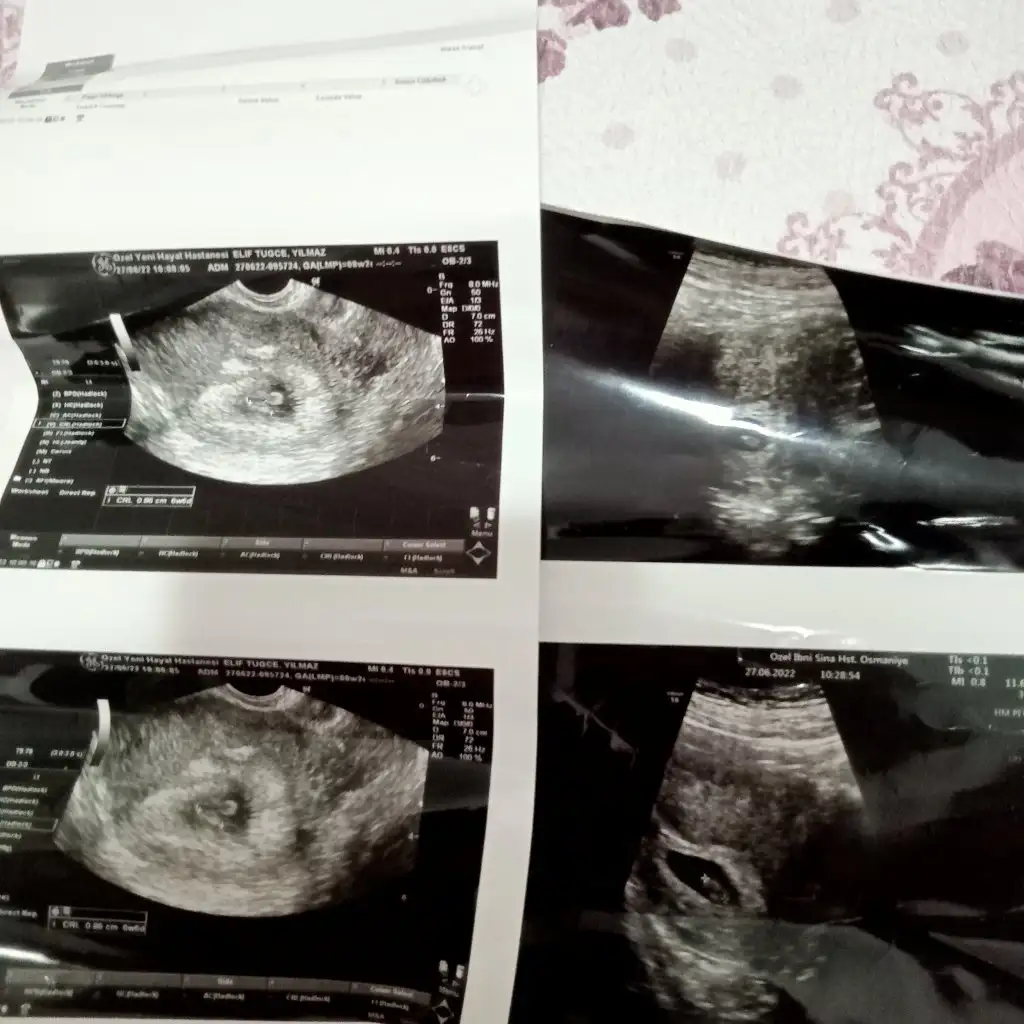

biri paşa biri prenses gibiBenimkine de bakarmisiniz 8+3 karından ultrason ikiz gebelik

prenses gibiMerhaba karından 6+3 görüntü suan 8haftalıgız banada cınsıyet tahmını yapabılırmısınız:)